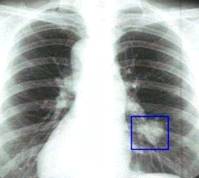

2. РЕНТГЕНОЛОГИЧЕСКИЕ МЕТОДЫ

Рентгенографические обследование -

является основным методом распознавания при опухолях легких, желудка, толстой

кишки. Поэтому этот метод применяется при обследовании онкологических больных.

Современная рентгенология широко применяет томографическое (послойное)

исследование и с контрастированием органа. За последние годы значительно

расширилось применение специальных методов исследования, таких как ангиография,

бронхография, повышающих эффективность диагностических исследований,

выполняемых в основном в стационаре. Флюорография, в особенности

крупнокадровая, играет большую роль в профилактических осмотрах населения.

Рентгенологическое обследование является одним

из основных, проводимых с профилактической целью. Каждый взрослый человек

должен проходить профилактические осмотры и рентгенографию легких не реже

одного раза в год.